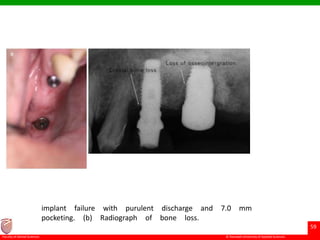

implant failure with purulent discharge and 7.0 mm

pocketing. (b) Radiograph of bone loss.